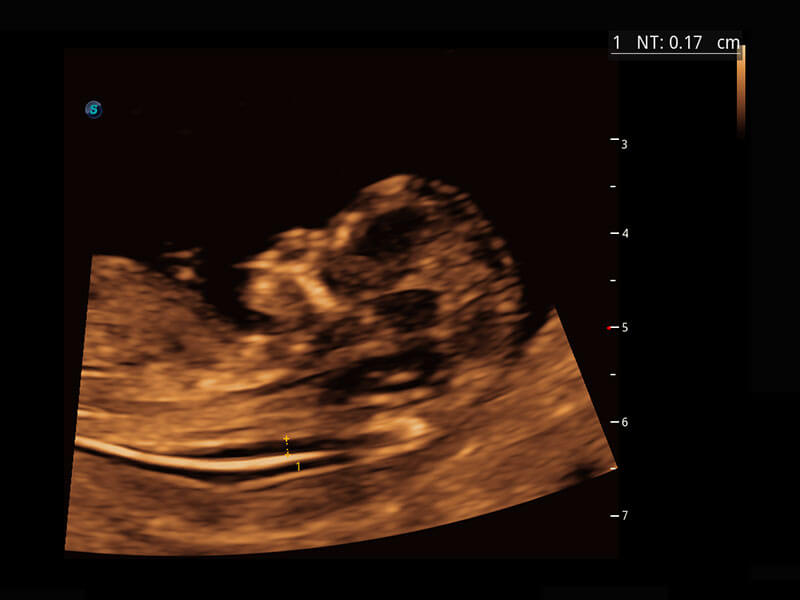

P60在胎儿早孕期超声筛查中为您带来优异的图像质量。

早孕-胎心